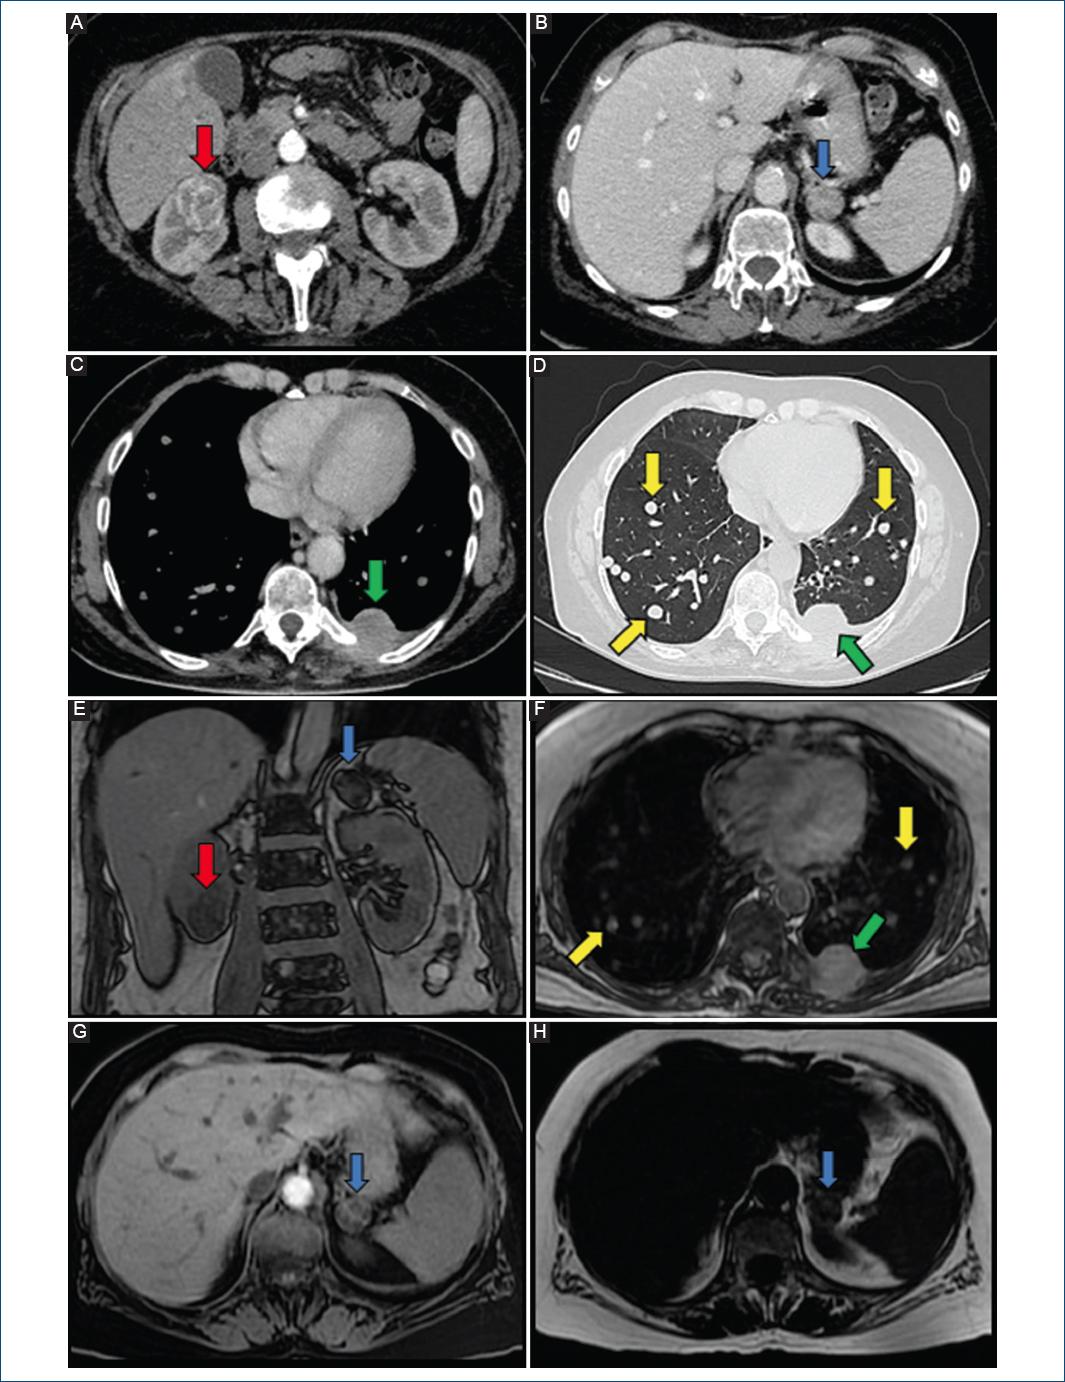

Fue derivada desde su ciudad de residencia por diagnóstico de posible endocarditis mitral, presentando pérdida de peso y sudoración nocturna de cuatro meses de evolución, descripción de una vegetación en valva posterior mitral y seis hemocultivos negativos. En nuestra institución se realizó ecocardiograma transtorácico, que evidenció masa móvil homogénea de 22 x 18 mm adherida a la valva mitral posterior de posible origen tumoral con protrusión hacia ventrículo izquierdo y generando insuficiencia mitral moderada (Fig. 1). No presentaba alteraciones en el electrocardiograma o el laboratorio. Se efectuó resonancia magnética (RM) cardiaca que informó la presencia de una masa en anillo mitral posterior de 20 mm hipervascular con captación y retención de contraste, y otra lesión similar pequeña en válvula aórtica (Fig. 2). Ante la sospecha de metástasis cardiaca, se realizó tomografía computarizada (TC) de abdomen y pelvis que detectó una masa isodensa heterogénea de 32 x 30 mm en el polo renal inferior derecho con necrosis interna y captación de contraste periférico, y un nódulo heterogéneo hipercaptante de 20 x 18 mm en glándula suprarrenal izquierda, ambos de origen neoformativo (Fig. 3). Se realizó TC de tórax que evidenció una masa hipercaptante subpleural a nivel basal posterior izquierdo de 29 x 28 mm que infiltraba los tejidos blandos y músculos intercostales adyacentes, además de múltiples nódulos pulmonares de hasta 5 mm compatibles con secundarismo (Fig. 3). La TC de encéfalo resultó normal. Se realizó RM de abdomen con contraste que detalló que la masa renal era compatible con neoplasia primaria y que el nódulo suprarrenal era compatible con secundarismo (Fig. 3). Se realizó biopsia renal, de una lesión pulmonar y de las subpleurales, compatibles con un carcinoma renal papilar de células claras con inmunohistoquímica positiva para vimentina y citoqueratina 7 en forma difusa y con patrón cup-like con anhidrasa carbónica IX. Se interpretó como carcinoma renal avanzado, con metástasis cardiacas mitral y aórtica (sin invasión de la vena cava), pulmonares, subpleurales y suprarrenal contralateral.

Figura 3 Imágenes de tomografía de tórax y abdomen con contraste endovenoso (A-D), y de resonancia magnética de abdomen con contraste endovenoso (E-H). Se observa el tumor primario renal derecho con necrosis central (flechas rojas), una metástasis en glándula suprarrenal izquierda (flechas azules), una metástasis subpleural que invade músculos intercostales (flechas verdes), y múltiples metástasis pulmonares bilaterales (flechas amarillas). En G y H se observa el comportamiento de la metástasis suprarrenal (flechas azules) mediante secuencias LAVA-Flex con supresión de agua y grasa, respectivamente.